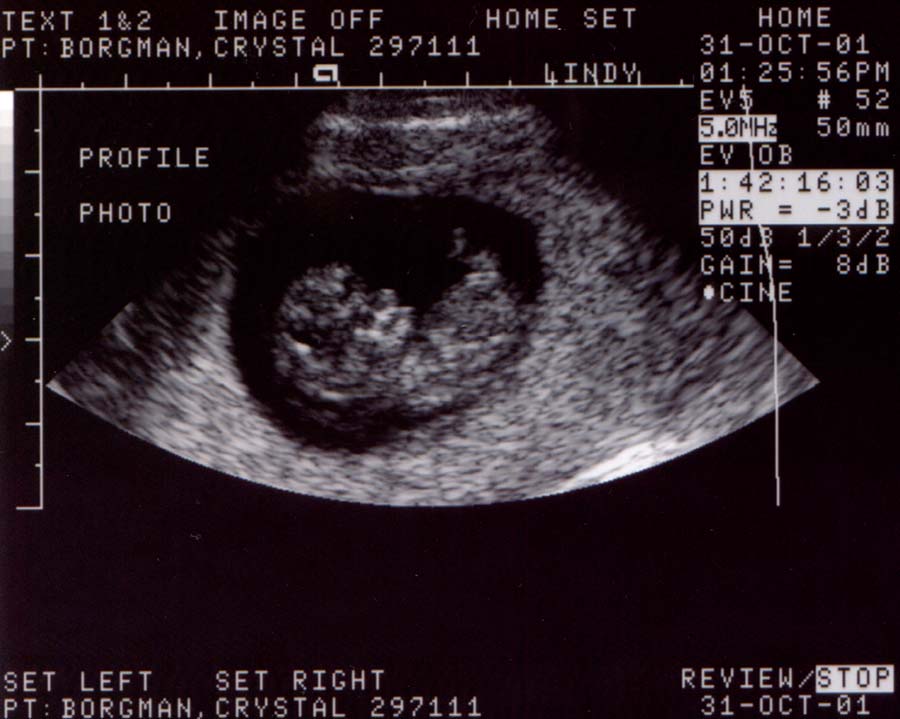

First ultrasound.

The baby looks great! It was moving around and having

a good old time. It measured at 10 weeks and 4 days,

or 37 millimeters (about 1 1/2 inches), which is just

about right. The heart rate was 188 bpm and very strong.

Looks like we've got a keeper.

Ultrasound Pictures:

Photo from top of

head looking down, hands are together

Large

- 900x700 pixels / 68K

Small

- 450x350 pixels / 28.8K